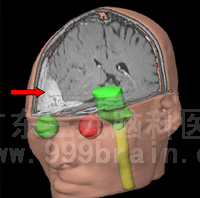

治疗前可见颅内转移癌(红色箭头处)

肿瘤空间位置示意图(箭头位置) 肿瘤三维重建示意图(箭头位置)